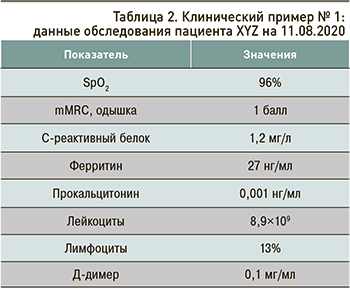

Данные обследования пациента на 11.08.2020 приведены в таблице 2.

Тест ПЦР на SARS-CoV-2 от 10.08.2020 отрицательный.

На контрольной мультиспиральной КТ сохранялись остаточные изменения легочной ткани, соответствующие поражению при COVID-19, КТ-3.

При выписке пациенту были даны следующие рекомендации.

1. Дыхательная гимнастика.

2. Расширение двигательного режима.

3. Массаж грудной клетки, вибромассаж.

4. Эноксапарин натрия – 0,4 мл подкожно 1 раз/ сут.

5. С целью антифибротической терапии был назначен препарат бовгиалуронидаза азоксимер (Лонгидаза) 3000 МЕ внутримышечно на 2 мл лидокаина, курс – 3 мес.

По истечении 3 мес на картине КТ грудной клетки наблюдалось практически полное восстановление нормальной структуры легочной ткани (рис. 2).

Данные обследования пациента XYZ, проведенного 24.08.2020 и 09.11.2020, отражены в таблице 3.